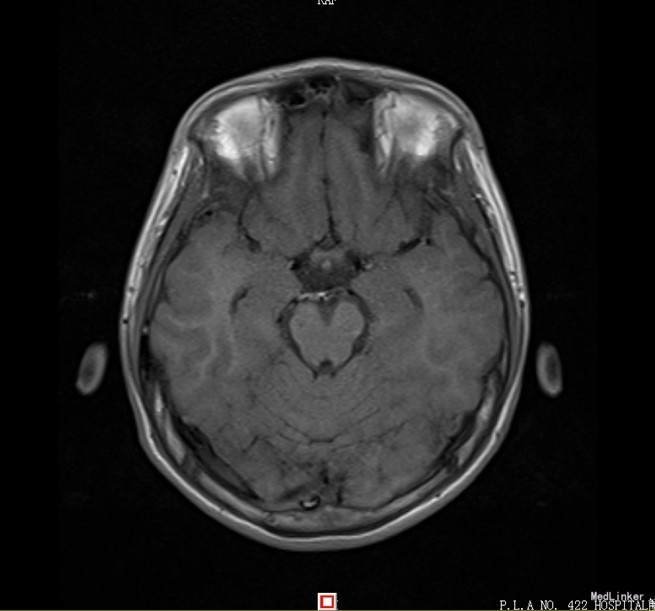

患者,男,14岁,患者自2周前不慎因外伤后出现头痛、头晕,为持续性钝痛,以后枕部为主,无发热畏寒,无视物模糊,无胸闷气短等不适,当时未引起足够重视,后患者感症状持续存在,遂告诉家人,家人送到我院门诊就诊,查头颅CT示:1、双侧大脑半卵圆中心区见多发斑片状低密度影,考虑血管间隙扩大可能,建议MRI复查;2、双侧额窦、筛窦炎。为进一步检查及治疗入院。患者目前精神欠佳,体力下降,食欲正常,睡眠正常,体重无明显变化,大便正常,排尿正常。既往体健。

患者目前诊断:1、脑外伤后综合征;2、半卵圆中心区血管间隙扩大;给予改善循环、营养神经等对症治疗,患者头痛、头晕症状明显好转。

经过1周治疗,患者头痛头晕症状基本消失。目前半卵圆中心区血管间隙扩大需要3月后复查。目前血管间隙扩大与此次外伤间有关系吗?其血管间隙扩大的机制是什么呢?